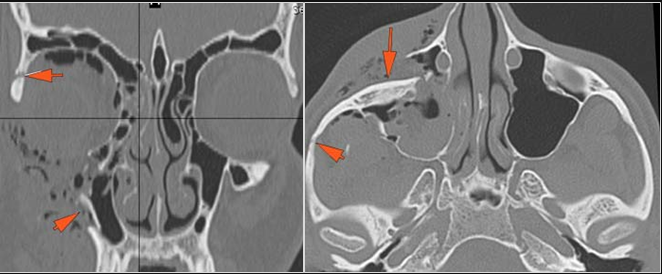

There is subperiosteal, epidural or subdural hematoma and/or pneumocephalus along the boney walls of the anterior or middle cranial fossa or elsewhere. |

Yes | NA |

The mesial naso-orbito-ethmoid complex is fractured. Specifically, there is bony injury of the nasal bones or the frontal process of the maxilla and the medial walls of the orbit are abnormal. |

There is injury of the ethmoid complex. Specifically, the ethmoid roof, olfactory fossa and the cribriform plate are fractured and/or significantly dehiscent. |

The frontal bone and frontal sinus inner and outer tables are fractured. |

LeFort type III, orbital zygomatic and orbital floor and fronto - naso-ethmoidal complex fractures with possible injury optic nerve/sheath - extent described above.